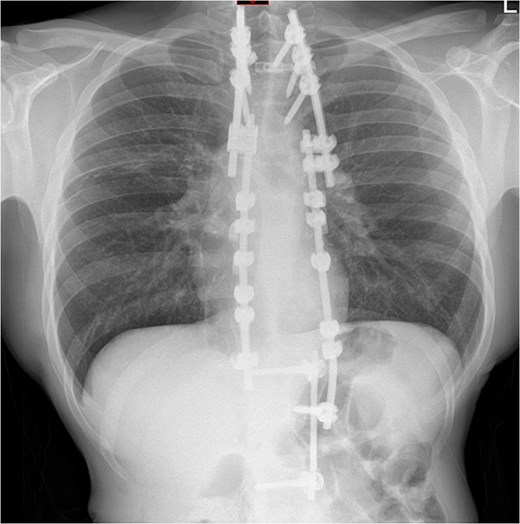

He had undergone excision and adjuvant radical radiotherapy of a pT3 N0 M0 sarcoma on the right-side of his neck 4 years earlier. Forty-six months after the original surgery, a routine chest radiograph identified a new nine-millimetre diameter right apical lung nodule (Fig. 1).

A monitoring radiograph 46 months after initial surgery noted a new nine-millimetre nodule in the right upper lung.

Four days after the surgery, the patient was re-admitted due to fever, cough, and some small-volume purulent discharge from his drain site. A repeat chest radiograph (Fig. 4) was unremarkable, and a wound swab was negative. He was empirically treated with 24 hours of intravenous antibiotics and given a short 4-day course to complete at home. It was felt by the team that a lower threshold for treatment of infection would be appropriate, given his diagnosis of CIP. He was discharged 1 day after re-admission and made a good recovery.

Repeat chest radiograph on re-admission to hospital with fevers and tachycardia.